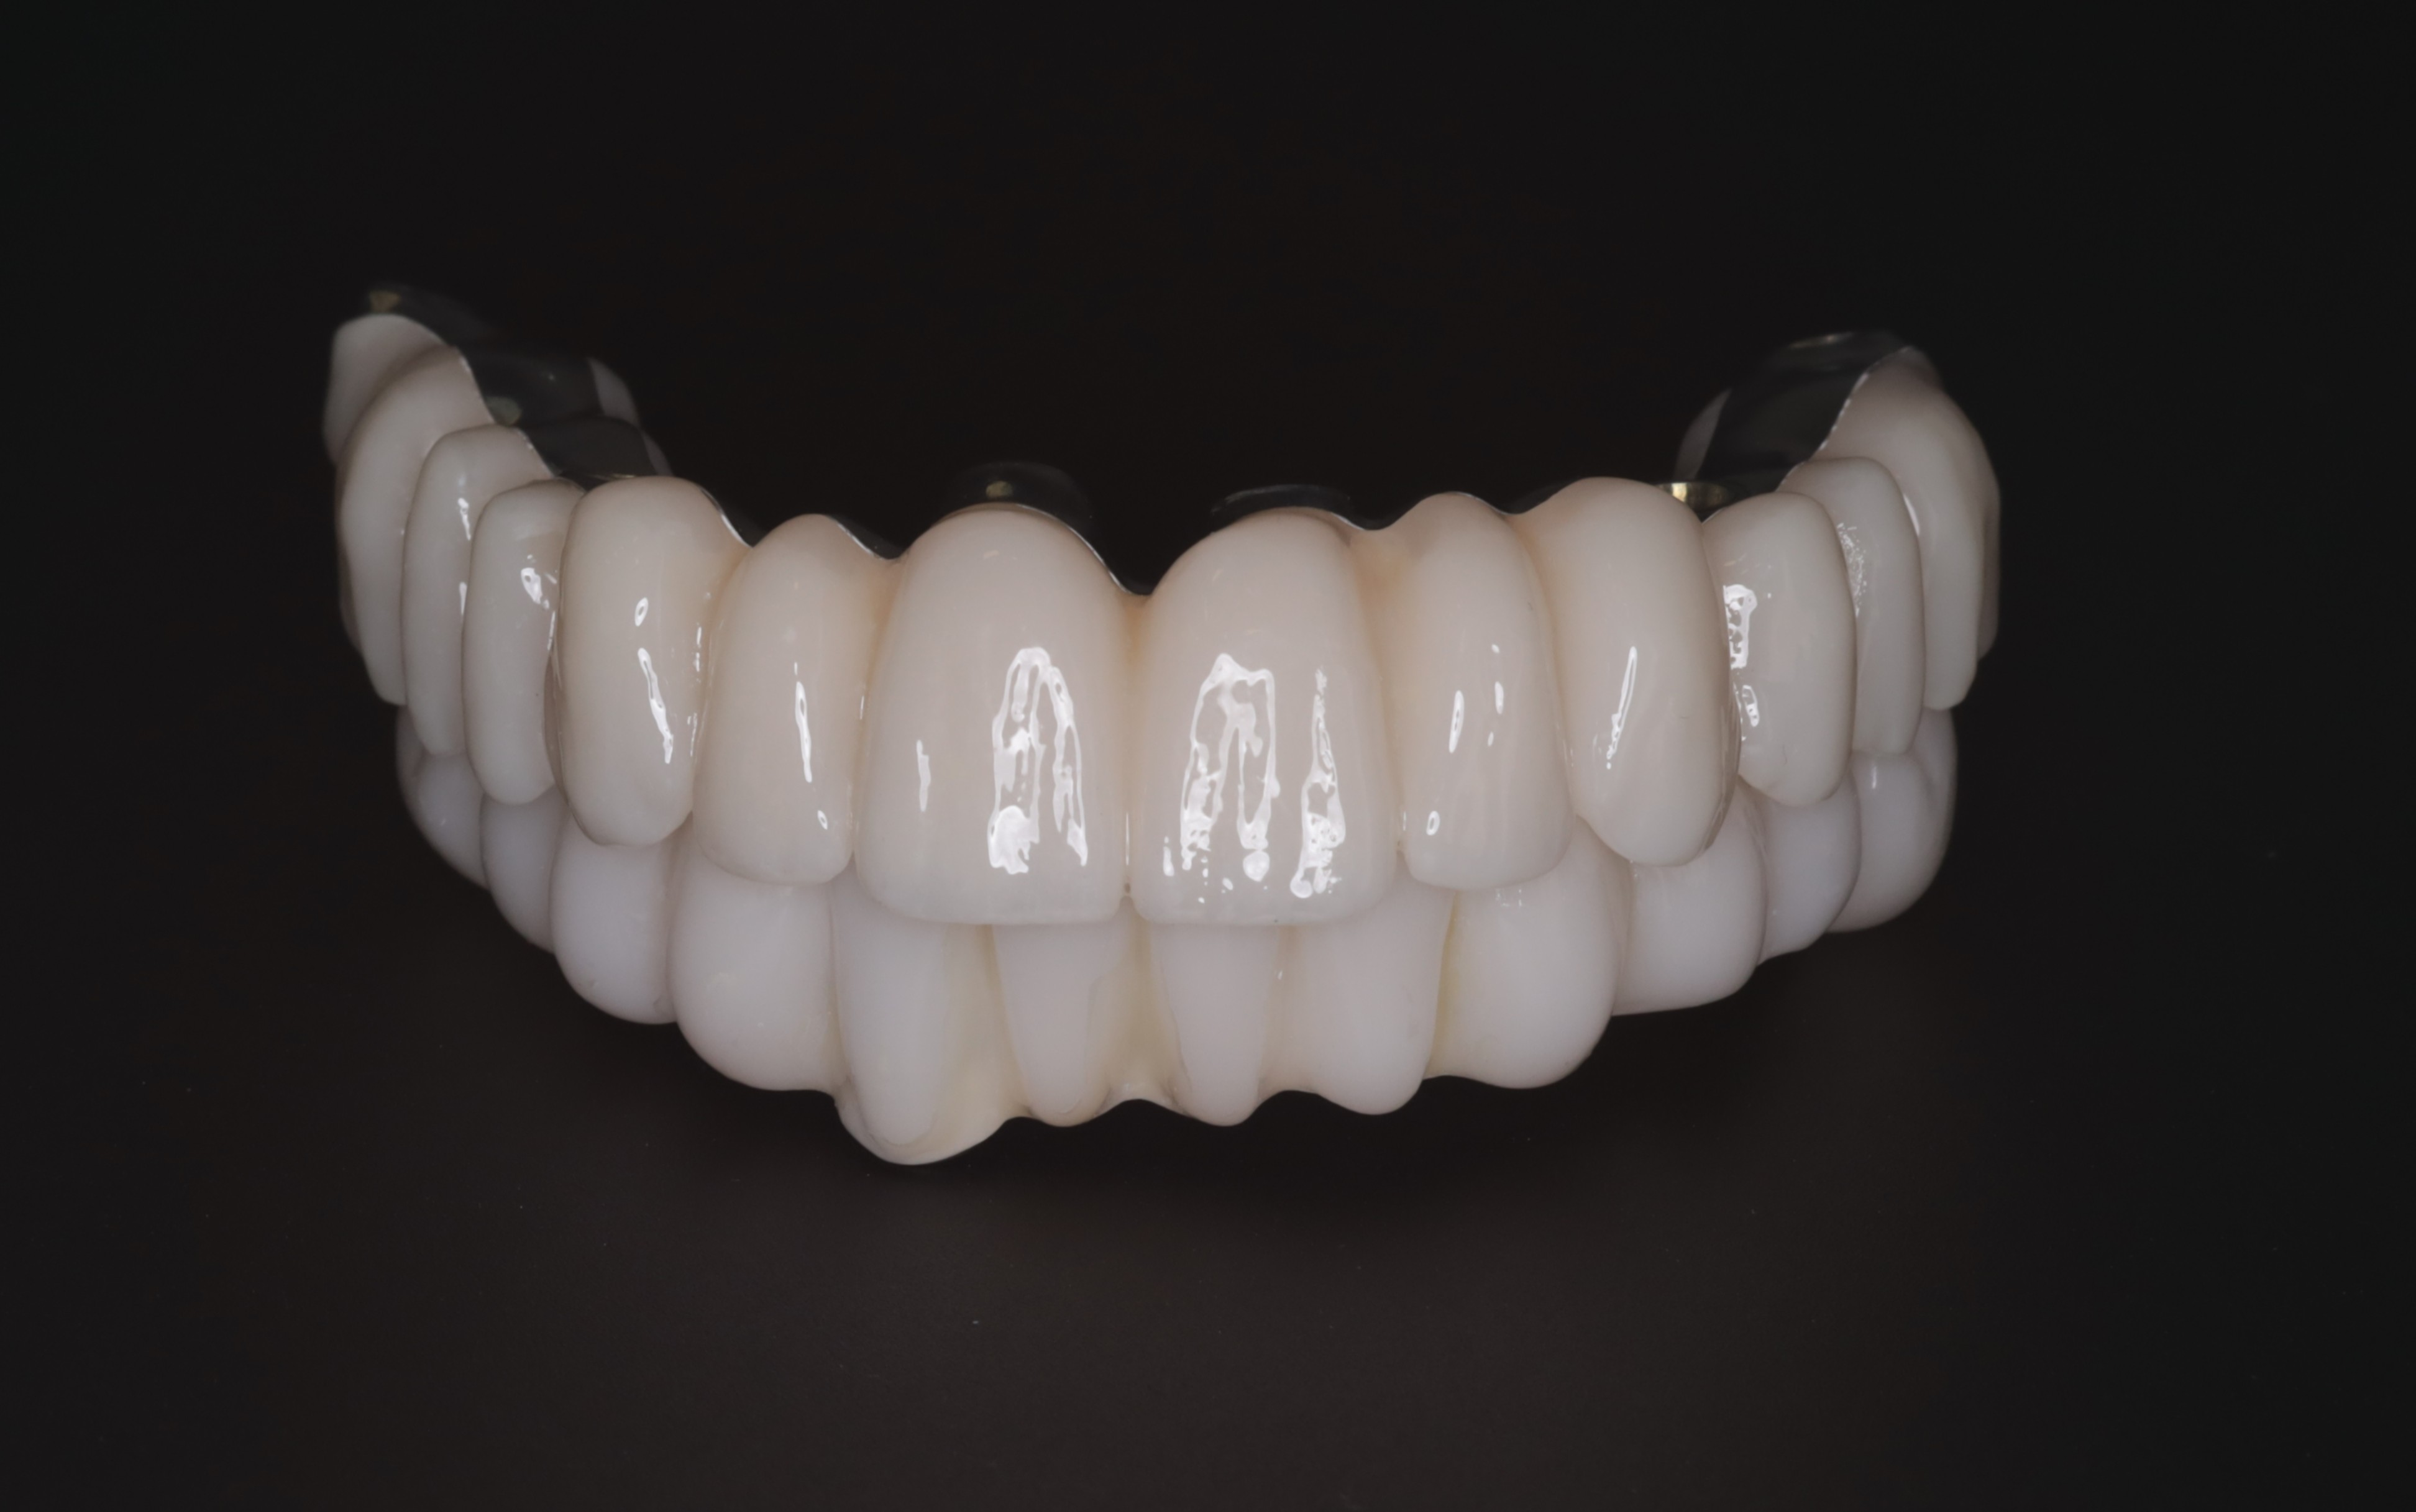

The final restorative phase utilized a repeat IPG scan to ensure micron-level accuracy for the definitive frameworks. The maxilla was restored with a zirconia bridge on a titanium framework, while a metal-composite framework was selected for the mandible. The definitive prostheses achieved a perfect passive fit and optimal seating, successfully restoring both masticatory function and the patient’s natural aesthetic smile.